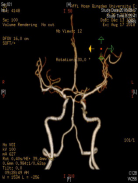

3天前无明显诱因突发剧烈头痛、恶心呕吐,神志清于2018年8月16日由外院转入青岛大学附属医院,CT示鞍上池中等量出血,以右侧侧裂池出血明显多。DSA和CTA示右侧ICA内侧壁有类圆形的囊状膨出,术前考虑为血泡样动脉瘤,术前Hunt-Hess分级II级。